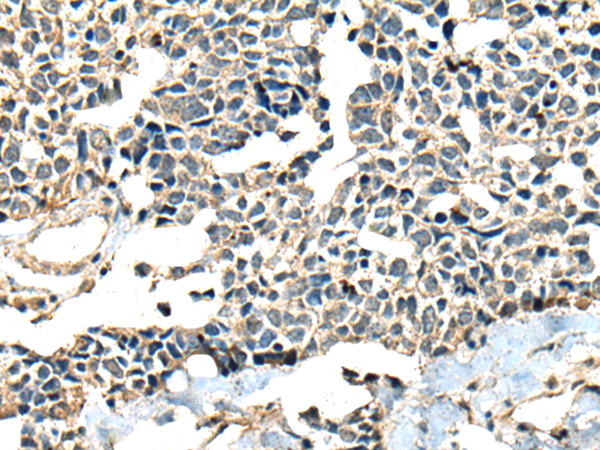

分类: 科研抗体货号: P09424别名: CNB; CNB1; CALNB1应用: IHC反应种属: Human, Mouse, Rat